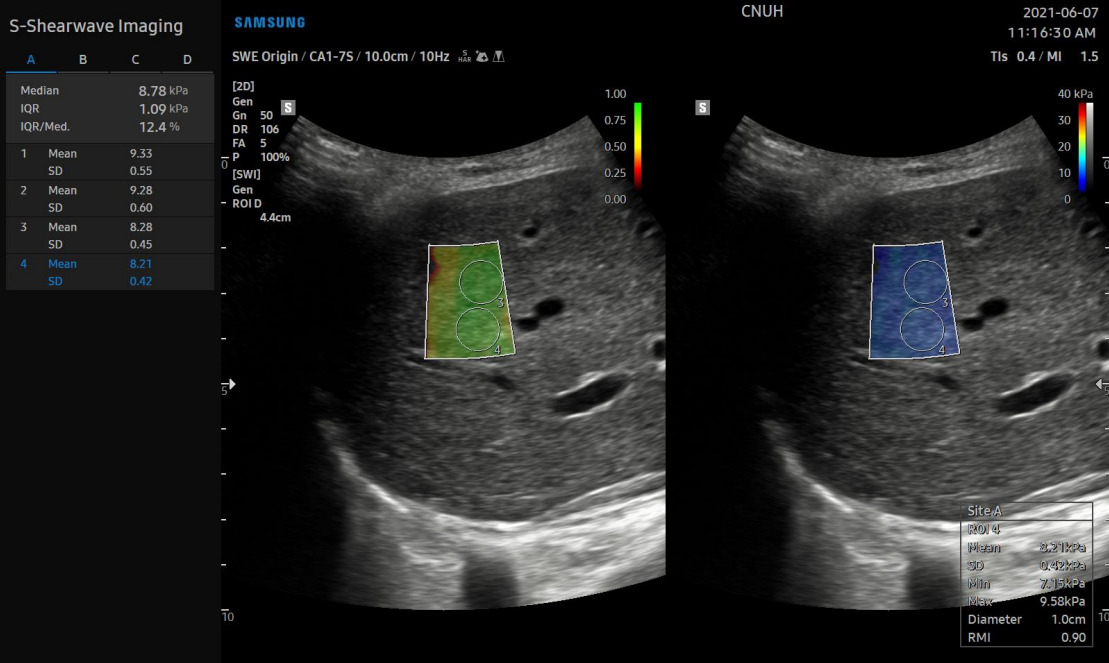

Особенности метода делают SWE портативным и выполнимым в различных клинических условиях. Так, современные ультразвуковые системы способны проводить эластографию печени (сдвиговой волны) с высокой точностью. Например, в УЗ системах Samsung функция эластографии называется 2D-SWE (S-Shearwave Imaging). Было установлено, что пороговые значения для диагностики начального фиброза, прогрессирующего фиброза и цирроза печени, составляют 6,82 kPa при ≥ F2, 8,63 kPa при ≥ F3 и 9,66 kPa при F4 соответственно. Данные значения актуальны только для систем Samsung.